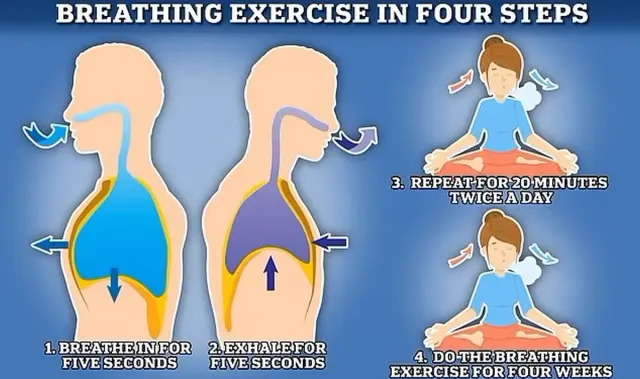

Este es el ejercicio de respiración. Es muy sencillo:

Simplemente hay que inhalar aire lentamente, durante cinco segundos, y exhalarlo también lentamente, durante 5 segundos.

Repetir el ejercicio durante 20 minutos, dos veces al día, durante un mes.